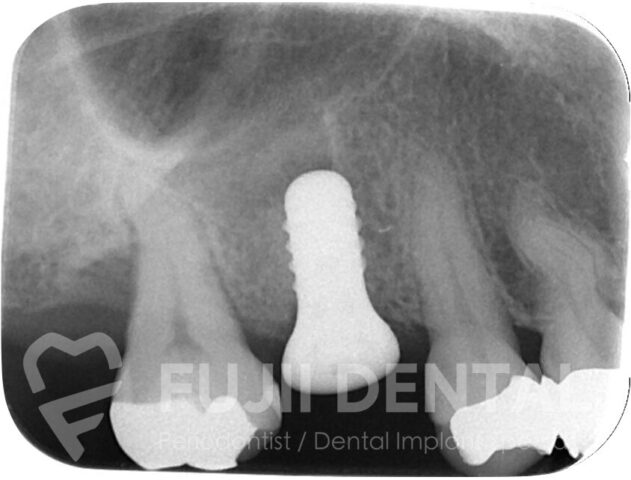

術後 3ヶ月後。骨がしっかりできていますので、もとの歯の形に近くなる太いインプラントを入れられます。また、8mmあった深い歯周ポケットが3mmと浅くなっており、歯周病は治癒したといえます。

侵襲なインプラント埋入手術

骨の治癒を待ったのち、インプラントを埋入。今回は「グラフトレス・オステオトーム」という、上顎洞(鼻の横の空洞)の骨を押し上げるテクニックを用いることで骨移植を避け、身体への負担、無駄な出費を軽減しました。

最小限の切開でダメージを最小限におさえてインプラントを設置。